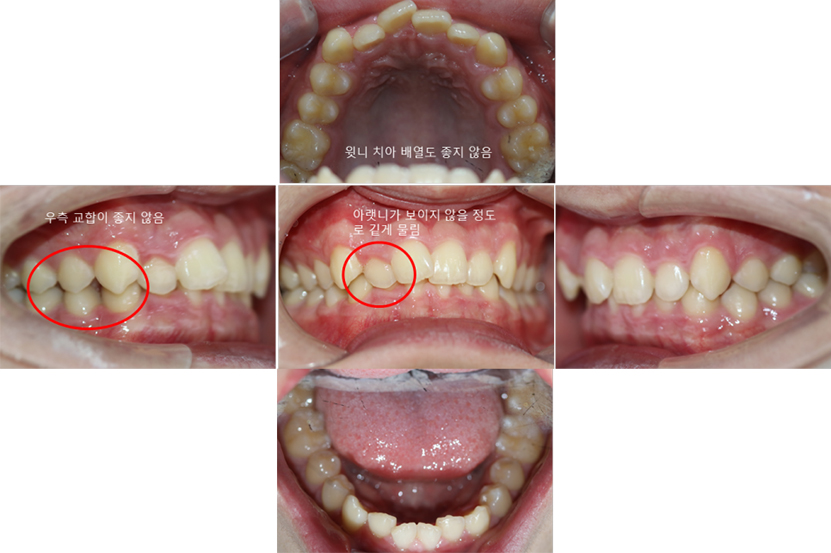

10대 남자 환자분이시고

앞니 배열과 깊게 물리는 것(과개교합을)을

해결하러 오셨네요.

배열도 안좋지만 오른쪽 교합도 깨져있고

치아가 너무 깊게 물리네요.